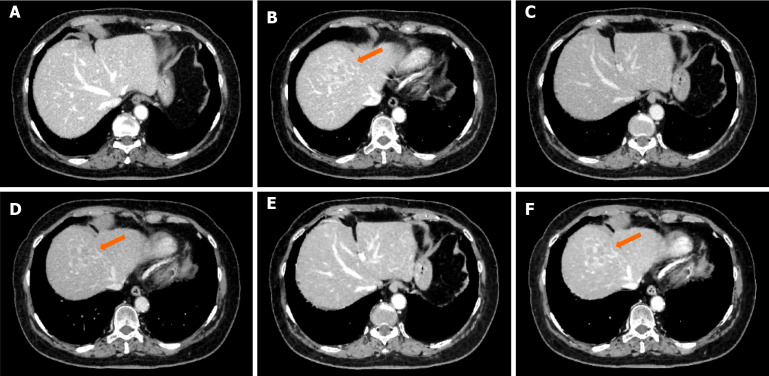

背景:三相动态计算机断层成像在肝脏区域特别有用。然而,造影剂动态成像的缺点是由于多次成像会增加辐射暴露。我们假设对比增强增强(CE-boost)技术可以增强平衡期(EP)图像的对比度,并产生类似于门静脉期(PVP)图像的增强,如果这是可能的,EP成像可以发挥与PVP成像相同的作用。我们还推测,这可能使三相动态成像转换为双相动态成像,减少患者的辐射暴露。目的:确定EP的CE-boost, CE-boost (EP)是否比常规图像有用。方法:回顾性分析2016年1月至2022年10月在我院诊断为肝癌的52例患者。从这些计算机断层图像中,从EP和平面图像生成CE-boost图像。我们根据对比噪声比(CNR)、信噪比和品质系数(FOM)比较了血管和肝实质的PVP、EP和CE-boost (EP)。还进行了血管可视化、病变显著性和图像噪声的视觉评估。结果:除肝实质外,CE-boost (EP)图像在CNR、信噪比和FOM方面均优于PVP图像。肝实质内CNR和FOM比较无显著差异(P = 0.62, 0.67)。EP和CE-boost (EP)图像的比较一致地倾向于CE-boost (EP)。在视觉评价方面,CE-boost (EP)图像在病变显著性方面明显优于PVP图像,在图像噪声方面明显优于PVP图像。CE-boost (EP)图像在门静脉节段性分支的血管显示和病变显著性方面明显优于EP图像,在图像噪声方面优于EP图像。结论:CE-boost (EP)图像质量与常规PVP和EP相当或优于常规PVP和EP。CE-boost (EP)图像可能提供与传统PVP相当的信息。

Methods: We retrospectively analyzed the cases of 52 patients who were diagnosed with liver cancer between January 2016 and October 2022 at our institution. From these computed tomography images, CE-boost images were generated from the EP and plane images. We compared the PVP, EP, and CE-boost (EP) for blood vessels and hepatic parenchyma based on the contrast-to-noise ratio (CNR), signal-to-noise ratio, and figure-of-merit (FOM). Visual assessments were also performed for vessel visualization, lesion conspicuity, and image noise.

Results: The CE-boost (EP) images showed significant superiority compared to the PVP images in the CNR, signal-to-noise ratio, and FOM except regarding the hepatic parenchyma. No significant differences were detected in CNR or FOM comparisons within the hepatic parenchyma (P = 0.62, 0.67). The comparison of the EP and CE-boost (EP) images consistently favored CE-boost (EP). Regarding the visual assessment, the CE-boost (EP) images were significantly superior to the PVP images in lesion conspicuity, and the PVP in image noise. The CE-boost (EP) images were significantly better than the EP images in the vessel visualization of segmental branches of the portal vein and lesion conspicuity, and the EP in image noise.